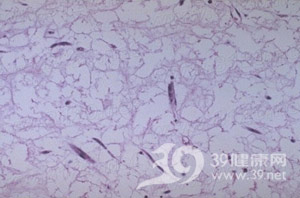

心臟粘液瘤腫瘤大小不一,多有蒂與心房或心室壁相連,外形多樣,外觀富有光澤,呈半透明膠凍狀。切面呈實質性,間有斑片狀出血區及充滿凝血塊的小囊腔。顯微鏡下可見腫瘤細胞呈星芒狀、梭形、圓形或不規則形,散在或呈閉索狀分布於大量粘液樣基質中,胞核多為單核也可呈多核瘤巨細胞。粘液肉瘤瘤細胞形態不一,胞核大,染色深,可見核分裂,瘤細胞可浸潤至小血管內形成瘤栓。